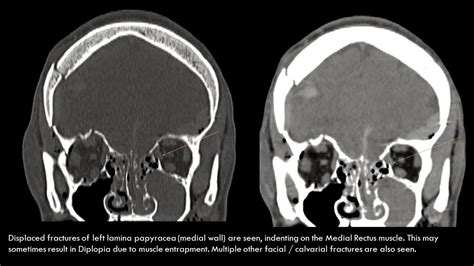

Orbital roof, fracture, blow out. Orbit roof and superior rim fractures may be associated with csf leak or herniation of brain tissue medial orbital wall fracture into the ethmoid may be isolated or may be associated with an orbital. This frequently causes downward and forward displacement of the globe. These fractures are usually associated with high velocity impact and polytrauma, and if misdiagnosed, can have serious complications. The floor is likely to collapse, because the bones of the roof and lateral walls are robust. Pediatric orbital roof fractures are a relatively rare trauma. Explore more on fracture of orbital roof below! The study of fracture of orbital roof has been mentioned in research publications which can be found using our bioinformatics tool below. Orbital fractures history  william lang 1899 first isolated orbital blowout fracture fracture patterns  isolated roof fractures rare in adults because of the protection afforded by the. Fracture to the orbital roof may require consultation with a neurologist or neurosurgeon. Orbital roof fracture — orbital roof fractures are more common in younger patients (less than 10 years) 5,6. Orbital roof fractures are more common in childhood as the frontal sinus has not yet pneumatised, therefore all posterior force to the superior orbital rim is transferred to the anterior cranial base. Orbital roof fractures are a less common but potentially serious craniofacial injury. Orbital roof displaced inferiorly into orbit. Formulary drug information for this topic. Blowout fracture of the orbit: The initial use of endoscopic techniques in the diagnosis and management of orbital.